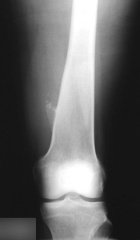

Case 10

55 year old man with left distal thigh pain for last six months to a year, it is worse with activity and relieved by rest